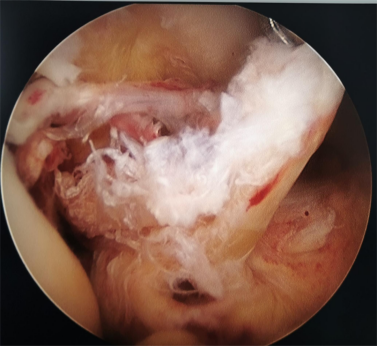

膝关节软骨损伤修复术